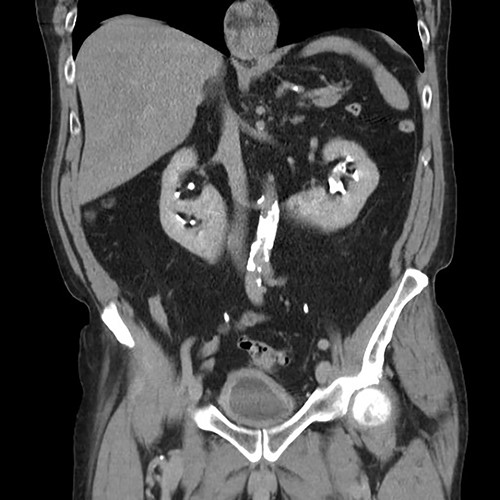

A 76-year-old gentleman with a background of benign prostatic hyperplasia, hiatus hernia, and anxiety was referred to the rapid access haematuria service following an episode of painless visible haematuria. Flexible cystoscopy did not reveal any concerning bladder lesions. CT Urogram demonstrated a horseshoe kidney with a filling defect in the left upper pole moiety suspicious for an urothelial carcinoma (Figs 1 and 2). The patient was subsequently referred to the urology services in a tertiary centre. Flexible ureterorenoscopy was performed, with findings of a likely urothelial carcinoma corresponding to the suspicious area on imaging. Biopsy of this lesion revealed a low grade urothelial cancer.

Coronal CT (urographic phase) demonstrating filling defect left upper pole.